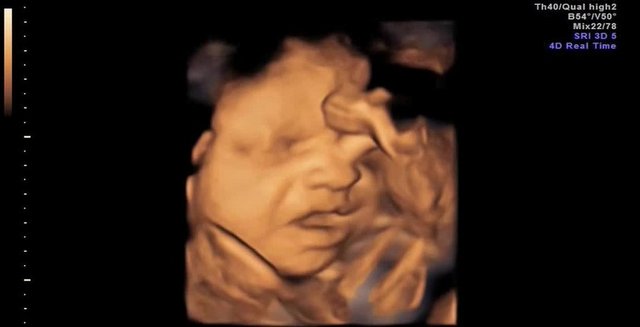

Ultrason çocuk için zararlı mı?Ultrason, görsel şov gibi algılanmamalı, kapsamlı 3 muayene normal olduğu gibi, doktor isterse fazladan olabilir.